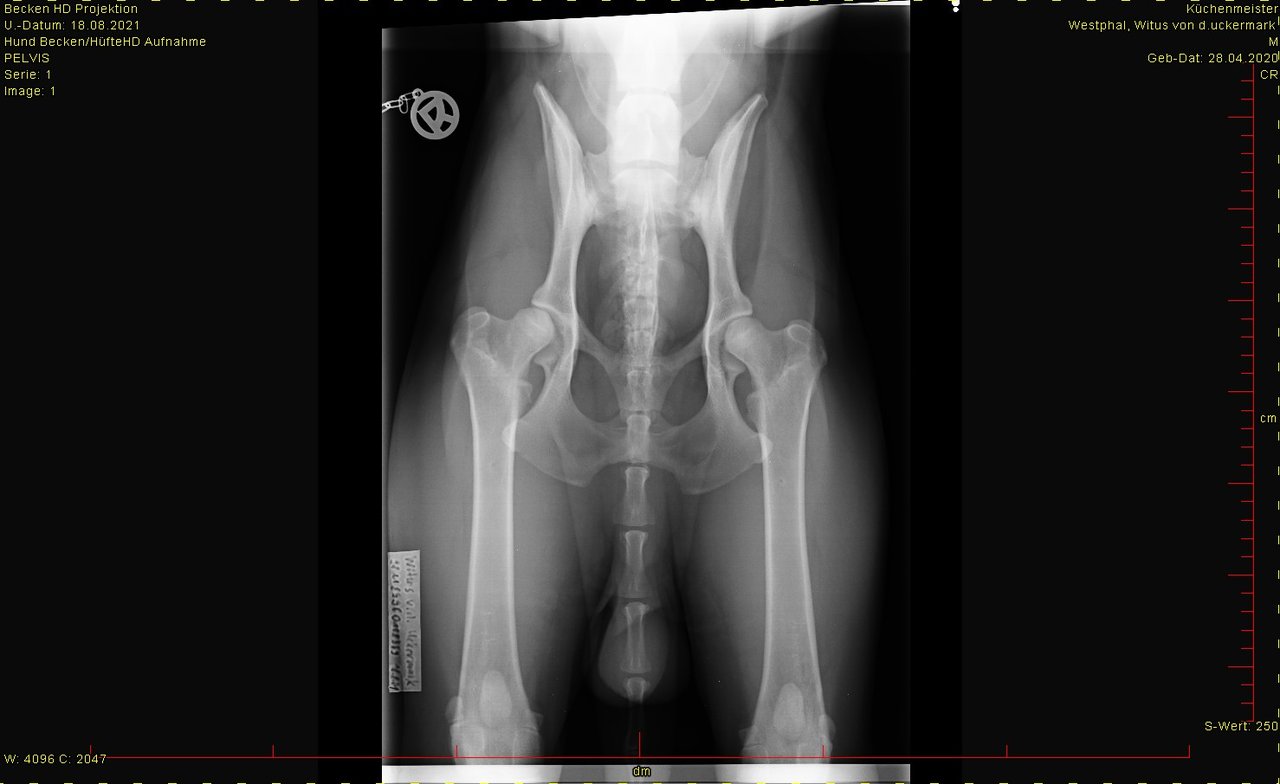

hier das Bild von der Hüfte. Ist HD-Aufnahme, kann man groß ansehen.

Was sagt Ihr dazu?

Bei den Ellenbogen traue ich mir keine Bewertung zu, finde aber, dass Hüfte und Rücken okay sind

Auf dem Bild sieht man ja beide Hüften und kann sie direkt miteinander vergleichen. Und dann sieht man gut die Unterschiede.

Die linke Hüfte wird wohl lt. TA eine leichte Abwertung bekommen. Was auch immer das heißt, HD fast normal? k.A. , mal sehen.

ED hat er nicht, LÜW sah auch ok aus.